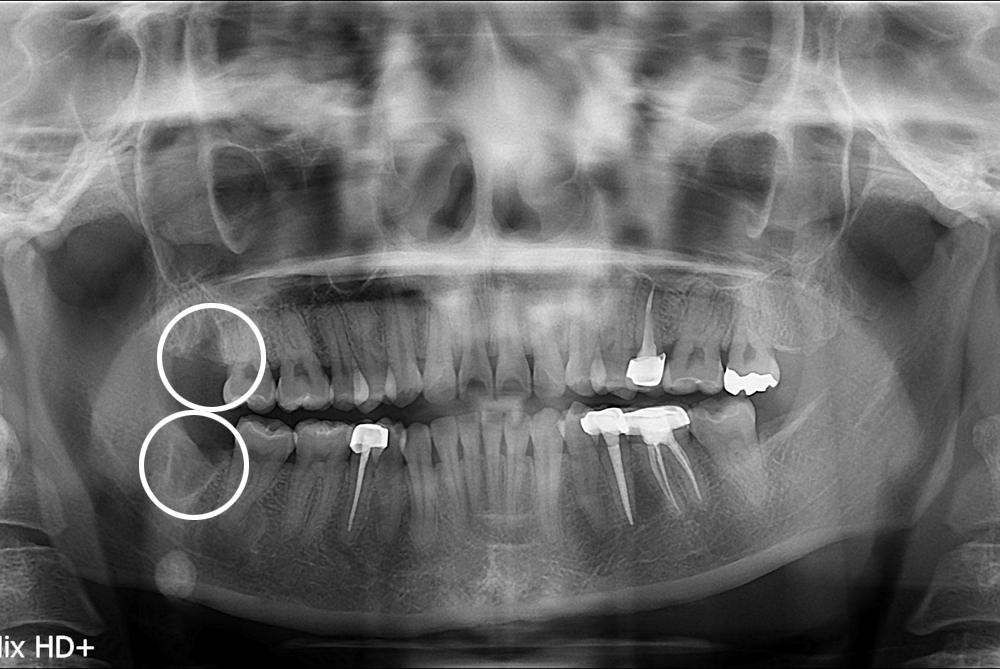

[사랑니] 난발치 사랑니 발치

치료후 : 2017-03-16

세종치과는 구강악안면외과학 박사이신 원장님이 발치하는 치과입니다.